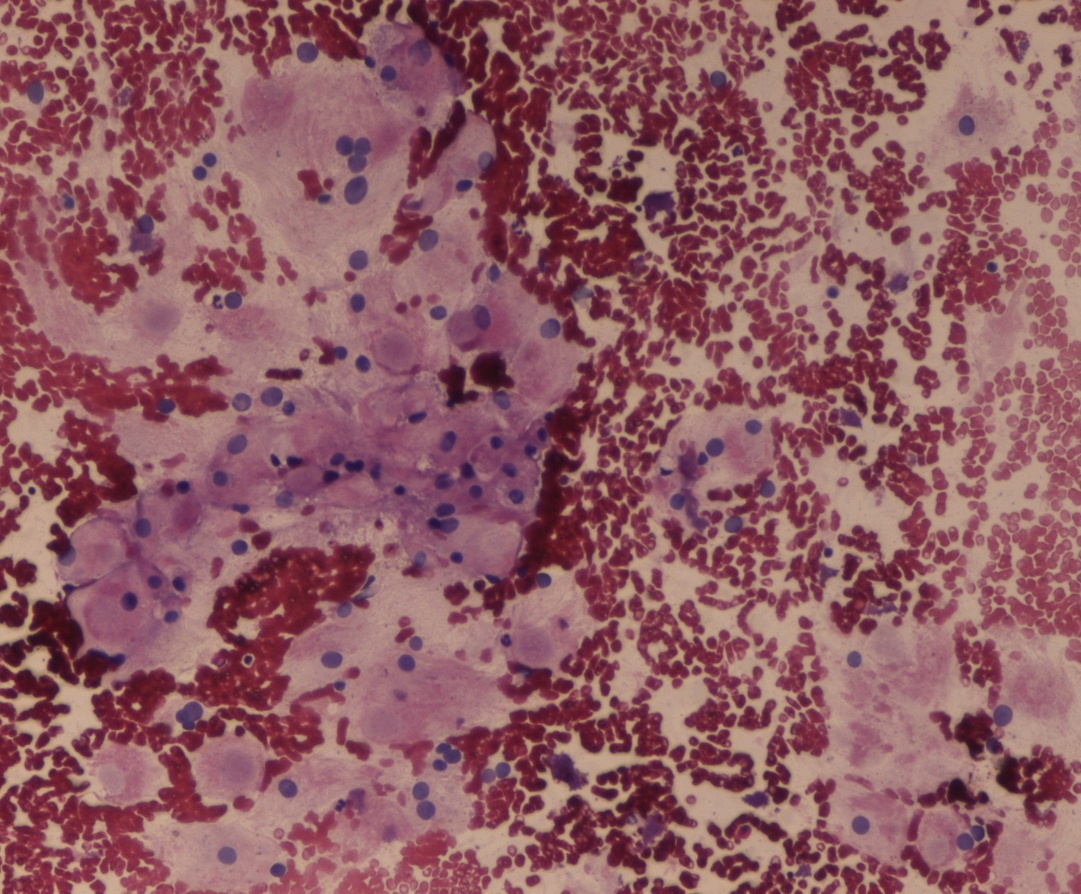

Alveolar soft part sarcoma (ASPS), a malignant soft tissue tumor with unknown etiology, predominantly occurs in the head and neck region, mainly the tongue and the orbit. The characteristic histopathological feature includes alveolar or pseudoglandular pattern, with PAS-positive, diastase-resistant intra-cytoplasmic inclusions. Primary therapy is total resection and adjuvant chemoradiation therapy. The present case study describes a rare case of ASPS of the anterior chest wall in a 15-year-old patient, diagnosed on fine-needle aspiration cytology. Total resection of the tumor with chemo-radiotherapy was performed and the follow-up after 2 years showed neither local recurrence nor distant metastases.